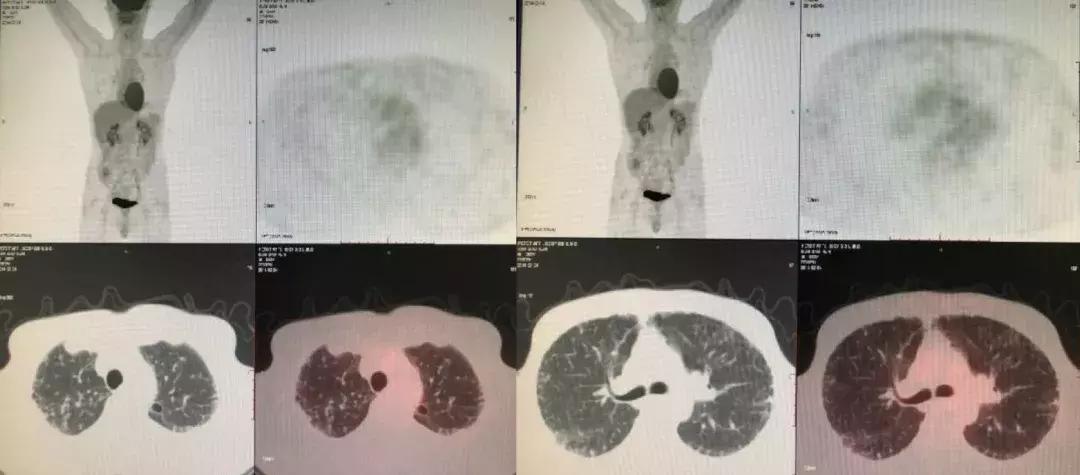

2014-02-21(入院第2天)胸部CT:

发现与2013-10-12胸部CT相似,主要还是以双上肺和胸膜下为主的网格状影,其次右下肺有片状影,可看到充气支气管征。

由于右下肺有结节,我们认为不排除肿瘤的可能性,所以做了PET-CT。

PET-CT(2014-03-04):肺间质改变,右下肺结节,SUVmax1.3。SUV小于3.5恶性肿瘤可能性小,故不考虑恶性肿瘤所致间质性肺炎。